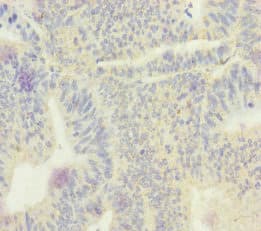

Echs1 Antibody Ab235835  Immunohistochemistry Formalin Pfa Fixed Paraffin Embedded Sections Img22156